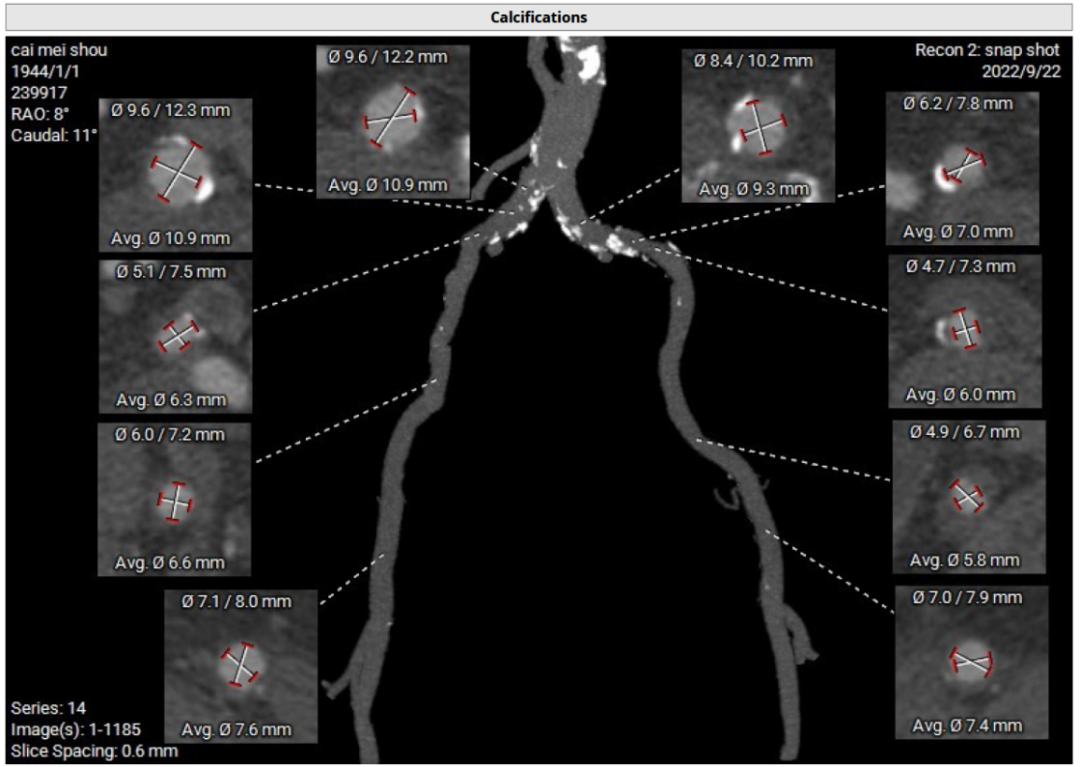

CT评估及手术策略

患者为三叶式主动脉瓣,重度反流。瓣叶交界轻度钙化。瓣环周长76.3 mm,平均径24.3 mm。LVOT周长77.3 mm,平均径24.0 mm。瓣上3.8 mm、5.0 mm、8.9 mm处空间为76.8 mm、82.8 mm、78.3 mm。STJ 周长105.7 mm,高度23 mm,升主周长126.5 mm 增宽、瓦氏窦大。综上所述建议TAV 27 瓣膜。左右冠高度15.6 mm、17.2 mm相对瓣膜支架可,冠脉风险低。股动脉入路血管轻度迂曲,双侧股动脉分叉高度可。腹主动脉、双侧髂总动脉散在钙化斑块。右侧股动脉平均内径最小6.3mm,左侧股动脉平均内径最小5.8mm,建议选择右侧股动脉为主入路。